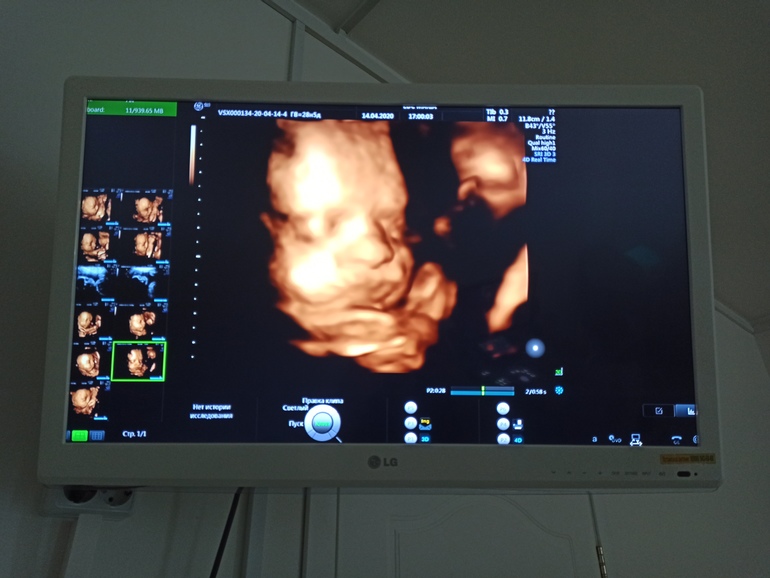

Делать и обязательно.

Вот моя 5 доча узи в 36 недель и родилась 3 денечка